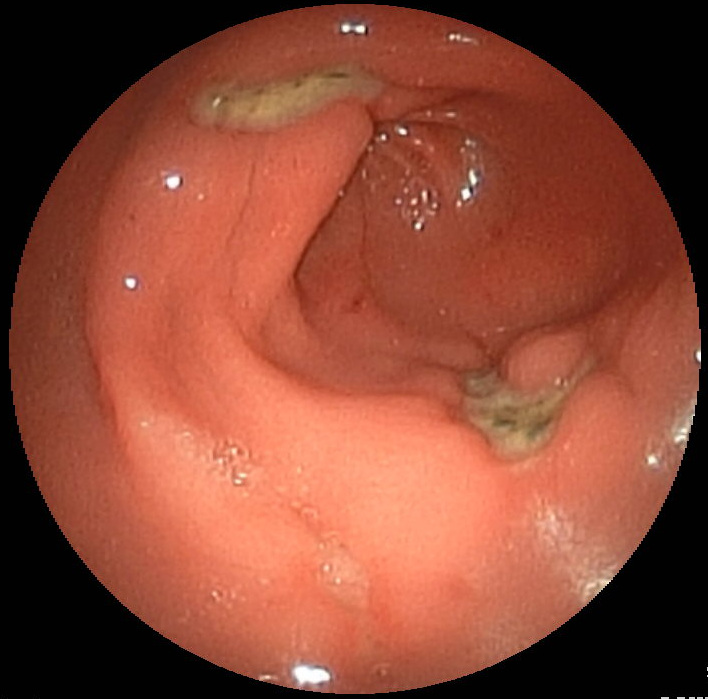

Example of Gastric Ulcer in the Antrum of the Stomach

This involves passing an endoscope through the mouth into the stomach in order to directly view the stomach. It can also be used to gain a view of the oesophagus and the duodenum. It is usually performed with the patient fully conscious or sedated, depending on the preferences of the patient.